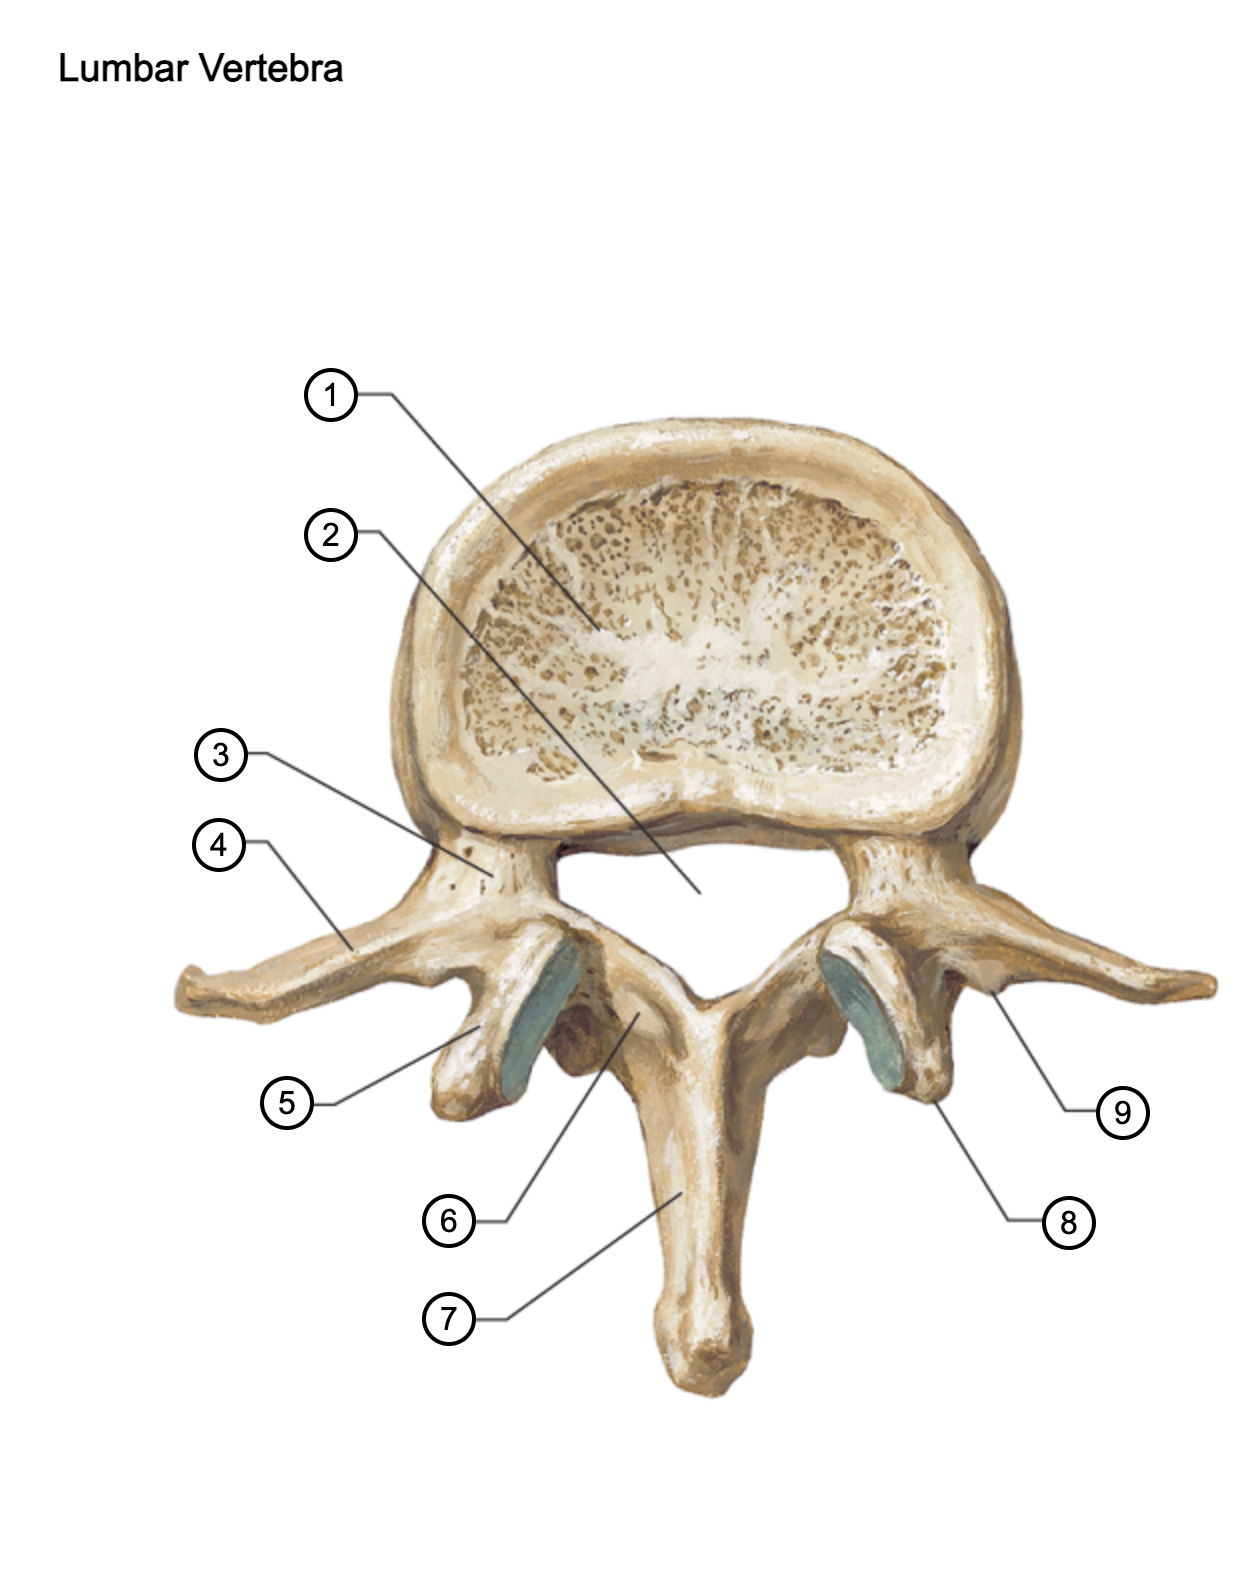

1

vertebral body

2

vertebral foramen

3

pedicle

4

transverse process

5

superior articular process

6

lamina

7

spinous process

8

mammillary process

9

accessory process